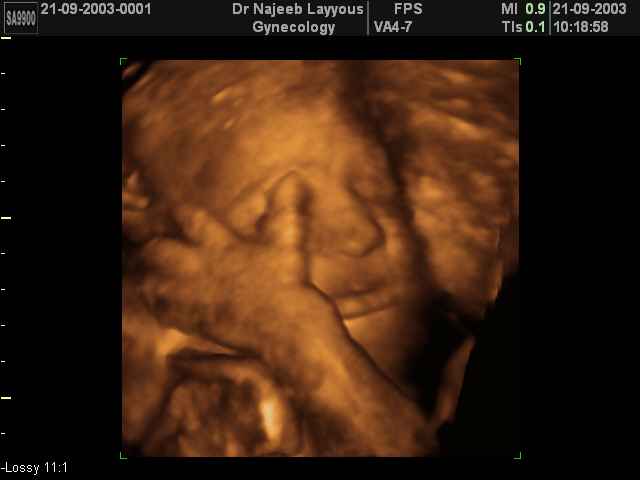

صور لوجه الجنين بجهاز الالتراساوند ثلاثي الأبعاد | الدكتور نجيب ليوس

صور لوجه الجنين بجهاز الموجات فوق صوتية ثلاثي الأبعاد